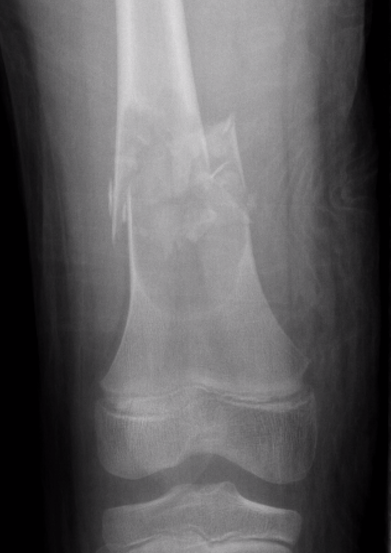

X-ray

Well-defined lucency

- thin sclerotic rim

- usually central

- thinned cortex with slight expansion

- thin internal septa

- can be multi-loculated

Fallen-Leaf (AKA fallen-fragment)

- with pathological fracture

- indicates that the lesion has no matrix and is fluid filled

DDx ABC

ABC

- eccentric (v central)

- width > physis

- can be very difficult to tell